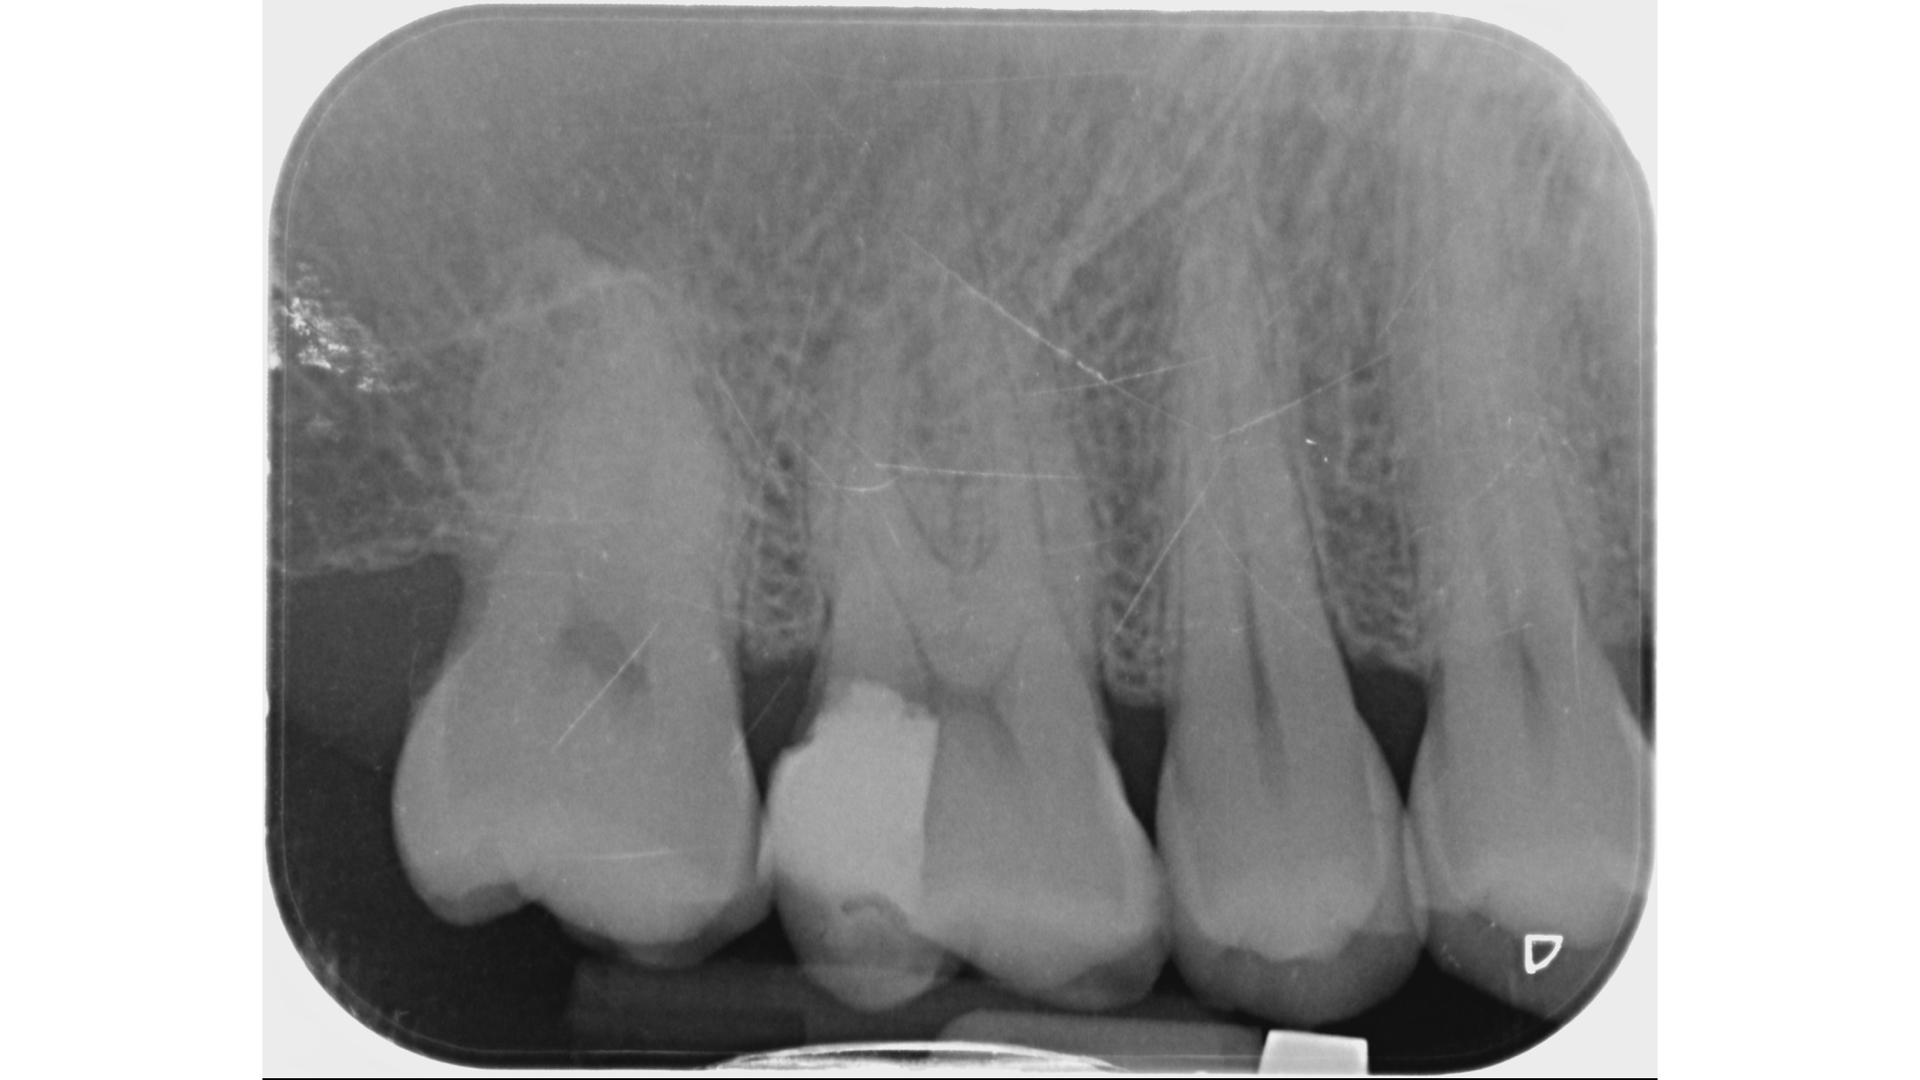

牙齒裂開後他院樹脂填補

X光片發現裂痕很靠近牙髓神經